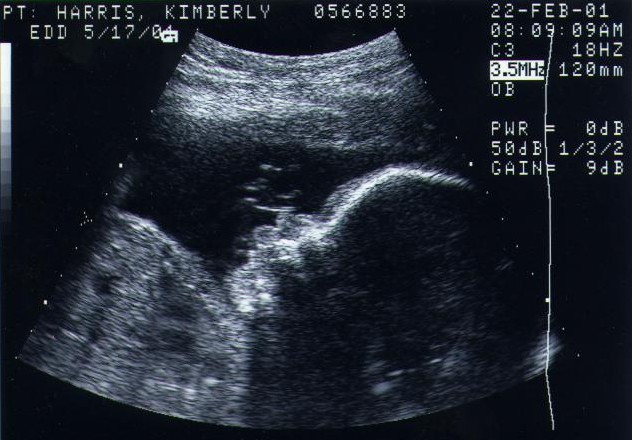

This is the ultrasound I had at 8 weeks and 3 days. That's my little baby boy!!!